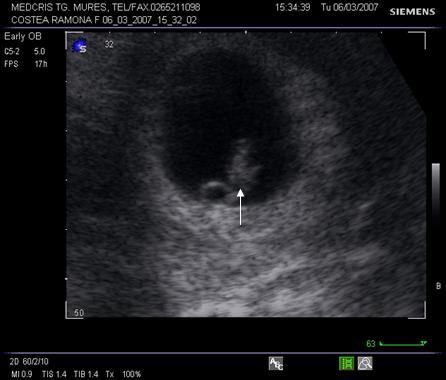

Fig. Nr.7. Sac gestational intrauterin ( cu sageata ) la ecografia transvaginala, coroana trofoblastica